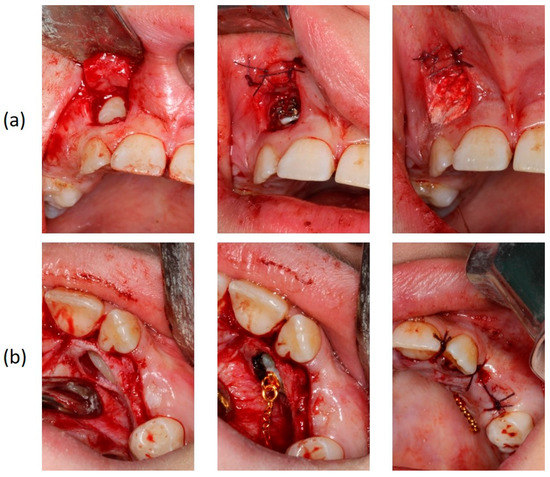

The orthodontic treatment was initiated with the canine exposure (Figure 5) and traction with light forces using a custom-made trans-palatal arch for anchorage purposes (Figure 6 and Figure 7). An open surgical technique (apically positioned flap) was used to expose the labially positioned right canine and a closed technique for the left, which was positioned palatally. Sectional mechanics were applied during treatment until the eruption of all permanent teeth (Figure 8). The upper lateral incisors were extracted after the successful eruption of the impacted canines and for aesthetic reasons. Subsequently, comprehensive orthodontic treatment was performed using fixed 0.018-inch-slot edgewise appliances. A lower lingual arch was placed to preserve the leeway space thus helping with the lower crowing. The progression of the archwire sequence was from 0.014-inch nickel-titanium to 0.016-inch Australian archwires. Class III light elastic forces were used bilaterally to help with space closure on the upper arch.

Figure 5. Surgical exposure of the upper right (a) and left impacted canines (b).